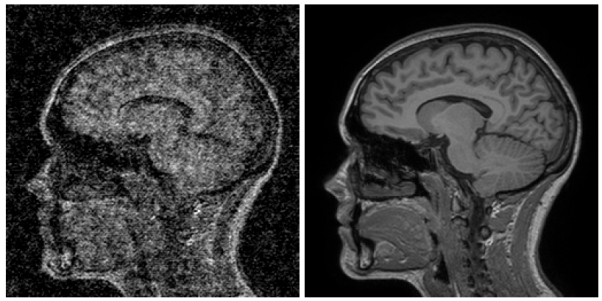

MRI noise – the image on the left is a simulated example of what the image on the right would look like if you scanned for 1/10th of the time. From here.

Super-resolution! This is an AI made image – they feed in the grainy one from above and try to produce the high quality one.

Here is the side by side comparison of the AI generated “denoised” image (on the left) and the diagnostic quality image (on the right).

If you look closely you can see that it isn’t perfect (there is still some blurring present), but the overall anatomy looks pretty reasonable. Nothing is horribly out of place, and maybe the blurring/quality issue is solvable with improved AI algorithms.